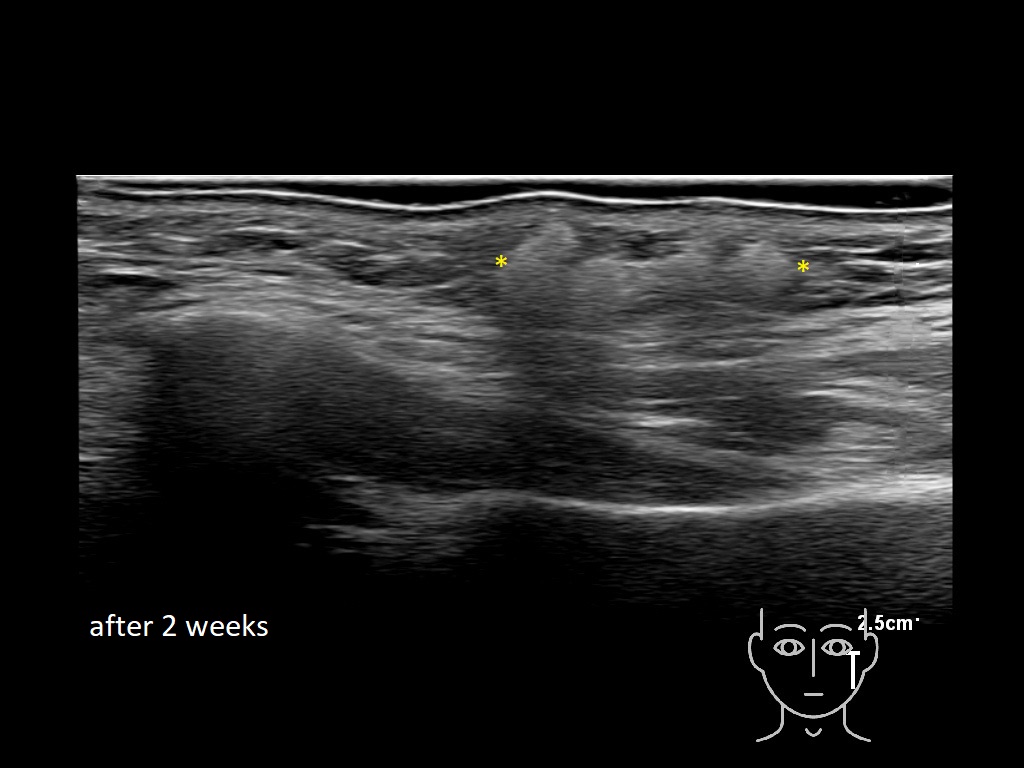

Draw in the image on the right where the fillers are located. To check if your answer is correct, please click on the secondary image.

Fillers

Draw in the second image below where the fillers are located. To check if your answer is correct, swipe the first image to the right.